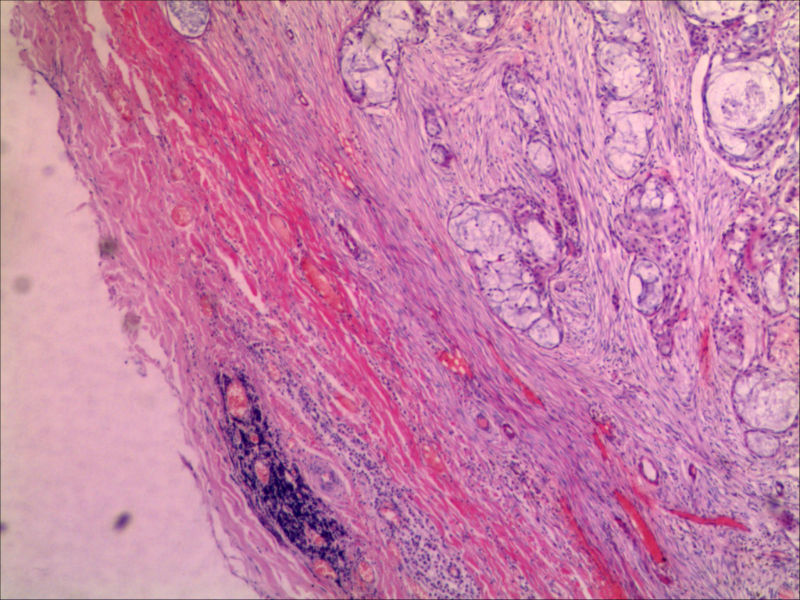

• 肿物有完整包膜求助

典型的黏液表皮样癌,低度恶性。

本例可以看到典型的产粘液细胞、鳞状细胞、中间细胞和透明细胞,因为产粘液细胞多,甚至形成粘液湖,加之包块似有包膜,分界清楚,应该考虑粘液表皮样癌(低度恶性)。